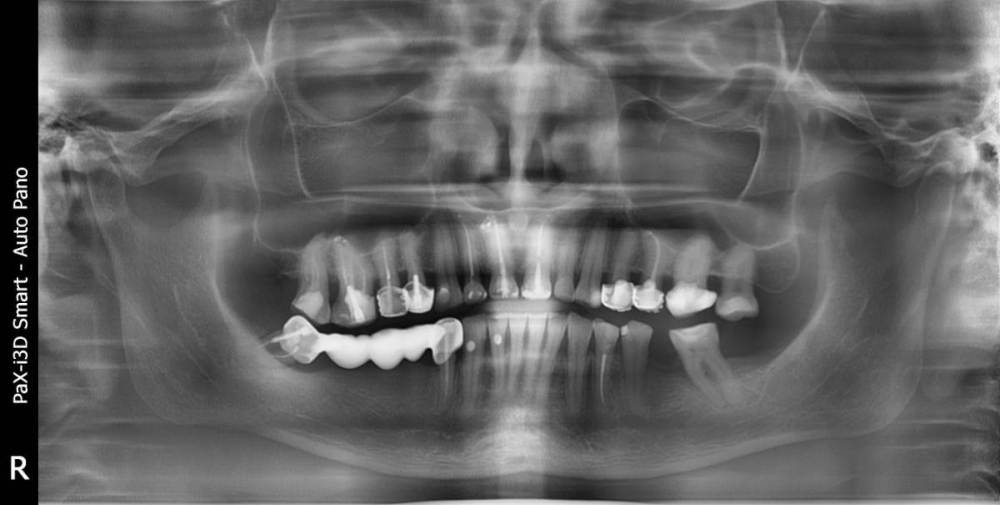

Вот с такой ситуацией обратилась к врачу, болел зуб мудрости.  Далее был сделан снимок (прилагаю фото решений- удаление опорных зубов с последующей заменой имплантами). PX20171201_162103_0000_000000FF.thumb.jpg.8c974cf49da3bb77db059abb91c7264c.jpg2018-01-24_013834.thumb.jpg.48a661d2a2f2d78a18d7b2906252d0a3.jpg2018-01-24_014845.thumb.jpg.0665ffa758959ace3ce9d7a8ff27421f.jpgпосле проведенных манипуляции появилась парастезия тройничного нерва, считаю это последствиями неверно установленного импланта, справедливо ли мое мнение?  Прохожу длительное лечение у невропатолога.  На крайнем визите врач отказал в помощи с этой проблемой и с обнаженным имплантом. (Прикладываю фото) 786267296_09_12_21.thumb.jpg.f332c30c240cb1ba19d2341b4f6014f1.jpg20220116_233530.thumb.jpg.c9cc82f18d25e9a905a2b7b1dc13eb8c.jpg20220116_232905.thumb.jpg.c3953c0b472c6e3ce1f46272ef507d2e.jpg1915694342_WhatsAppImage2022-08-20at19_39_20.thumb.jpeg.2099829af18d4d8c448126d5f323605f.jpegУ меня следующий вопрос:  верно ли назначенное лечение и насколько корректно установлены импланты, а также имелись ли противопоказания для установки имплантов, имея ввиду, что была убыль кости? Можно ли устанавливать импланты в таком случае?  прикладываю фото уже удаленного установленного на на импланты моста, правильно ли выполнен технически? (импланты пришлось удалить, а мост снять, чтобы сделать операцию по восстановлению кости, но уже в другой клинике. так как, как я писала выше, врач, установивший импланты отказал в помощи).

План лечения в виде удаления зубов и установки имплантов был назначен вам верно. Вариант с увеличением костной ткани и последующей имплантацией предпочтительней,чем ставить импланты без костной пластики. Но вариант,который делал первый доктор тоже не запрещен,видимо что то пошло не так